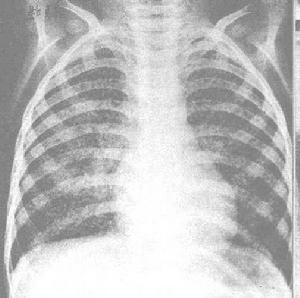

主要依靠病史、症狀、體徵、尤其是胸部X線檢查以及痰液結核菌檢查等,一般不難確診。多數患者在孕前已明確肺結核的診斷及進行過治療。在妊娠期檢查時,遇有低熱、盜汗、咳嗽、消瘦及肺尖部聽到濕羅音等臨床表現時,應想到肺結核的可能。通過胸部透視或攝片檢查可以明確診斷。

有人為減少X線對胎兒的影響,主張先行結核菌素皮內試驗,如為陽性,再進行胸部X線攝片檢查。但國內一般城市兒童已多有結核感染,對疑有肺結核的孕婦,應先以1/10萬稀釋液皮試,如陰性時,再用1/萬稀釋液皮試,如仍為陰性,則結核的可能性不大。若呈強陽性反應,則有輔助診斷價值。

3、X線檢查,慎做。

1、加強衛生宣教 做好卡介苗的接種工作。在肺結核活動期應避免妊娠;若已妊娠,應在妊娠8周內行人工流產,1-2年後再考慮妊娠。既往有肺結核史,或與結核患者有密切接觸史,均應在妊娠前行胸部X線檢查,以便早期發現及處理。